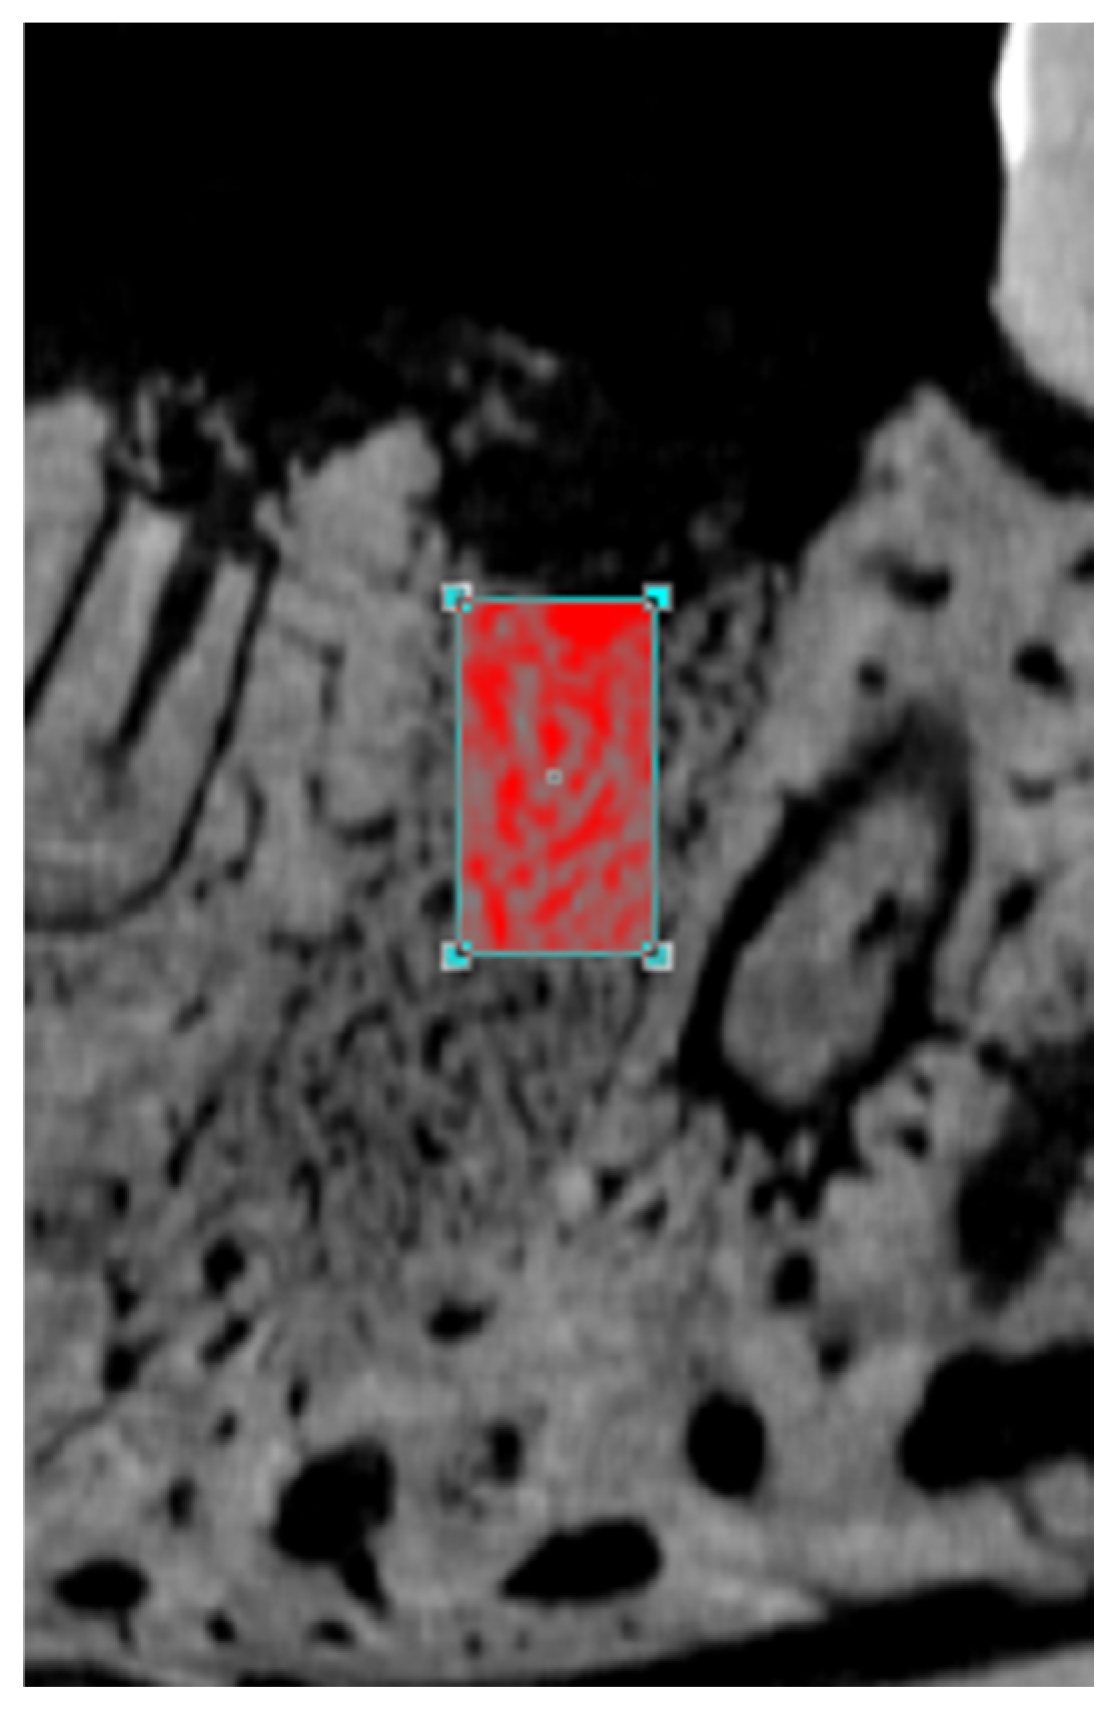

3.2. Micro-CT

3.3. Histological Analysis